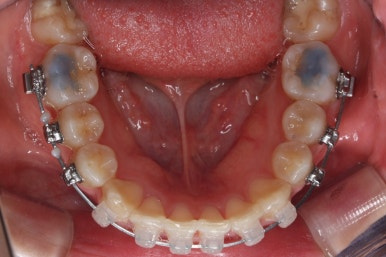

아랫니도 어느 정도 많이 가지런해졌습니다.

윗니를 계속 당겨 넣습니다.

만족을 하실 때까지 계속계속 넣고 그리고 입 안에서는 허락하는 만큼 계속 당겨 넣습니다.

이제 아래쪽도 당겨 넣습니다.

원하는 만큼, 허락하는 만큼 계속 당겨 넣습니다. 연산동교정치과에서는 비발치 돌출입 교정을 위해 총 4개의 미니스크류를 식립했습니다.

이제 거의 다 되감을 알 수 있습니다. 앞니의 뻐드러짐도 많이 좋아졌고 전반적으로 들어간 양도 적절해 보입니다.